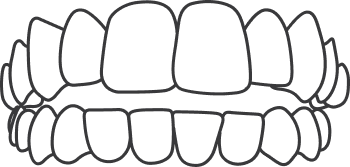

An open bite is where the front teeth do not overlap the lower teeth. This is caused by oral habits like finger sucking, tongue thrusting, or when the jaws don't grow evenly.